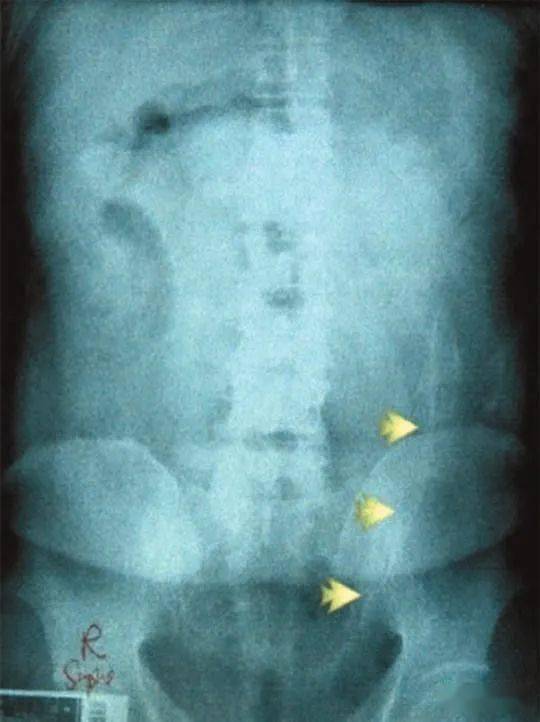

同样是菊花“偷渡” , 这位印度男子能藏2斤金条已经让人大开眼界 ,但事实证明 , 人类的能量超乎你的想象 。上个月 , 巴西某监狱一位男性囚犯肛门中被发现有 8部带电的手机 , 4根USB线 , 7个手机芯片还有1根充电器电线…他当时是刚到达监狱 , 接受电子检查 , 体内的电子装置直接被扫描仪显示出来了 。好家伙 , 这琳琅满目的电子产品 , 感觉在监狱里开个手机店都不成问题了 。

他这也是靠“非法偷渡”挣钱 , 把这些手机、充电线都包好了塞进屁股 , 通过人体运送进监狱 , 分给需要的狱友 , 交易完成之后他就能得到一笔相应的钱 。说是手机店好像也没什么不对??最后这个男囚不需要医疗帮助 , 自己把8部手机、充电线啥的都排出来了 。